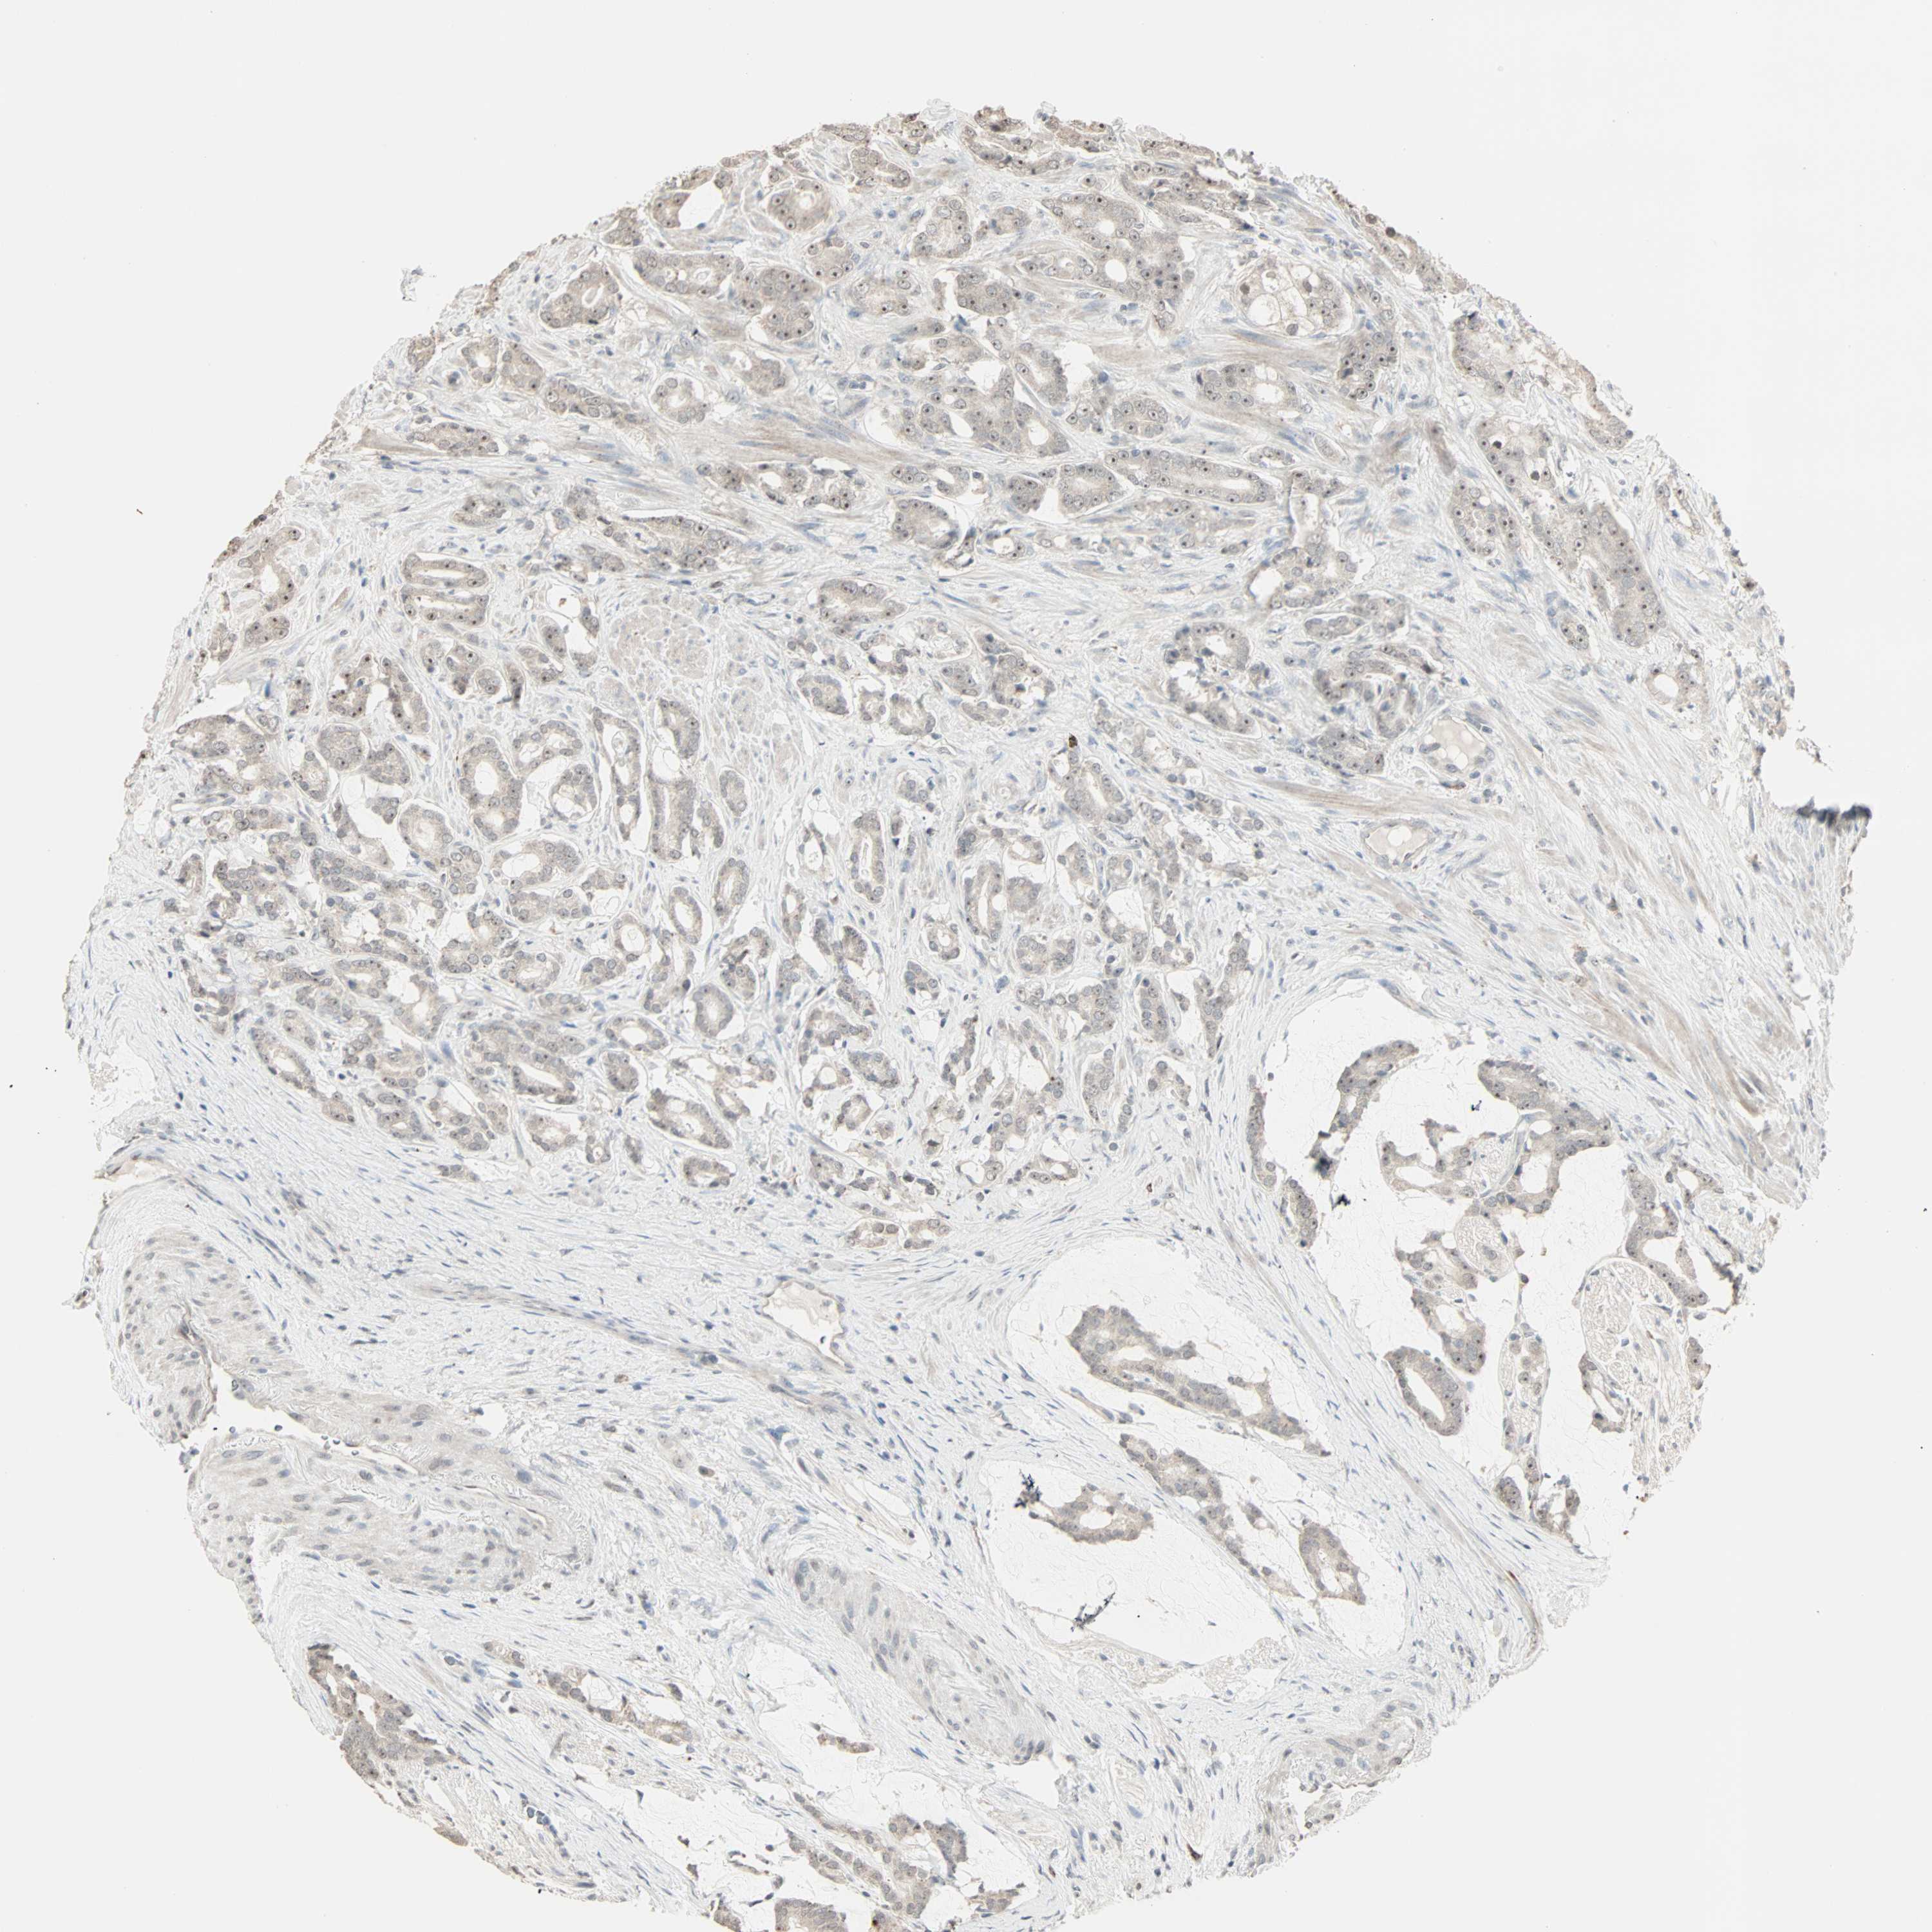

PROSTATE CANCER - Protein expressioni

A mouse-over function shows sample information and annotation data. Click on an image to view it in a full screen mode. Samples can be filtered based on level of antibody staining by selecting one or several of the following categories: high, medium, low and not detected. The assay and annotation is described here.

Antibody stainingi

Antibody staining in the annotated cell types in the current human tissue is reported as not detected, low, medium, or high, based on conventional immunohistochemistry profiling in selected tissues. This score is based on the combination of the staining intensity and fraction of stained cells.

Each image is clickable and will lead to virtual microscopy that enables deeper exploration of all samples and also displays staining intensity scores, fraction scores and subcellular localization as well as patient and tissue information for each sample.

Antibody HPA007610

Staining

High

Medium

Low

Not detected

Intensity

Strong

Moderate

Weak

Negative

Quantity

>75%

75%-25%

<25%

None

Location

Nuclear

Cytoplasmic/membranous

Cytoplasmic/membranous,nuclear

Adenocarcinoma, Low grade

Adenocarcinoma, High grade